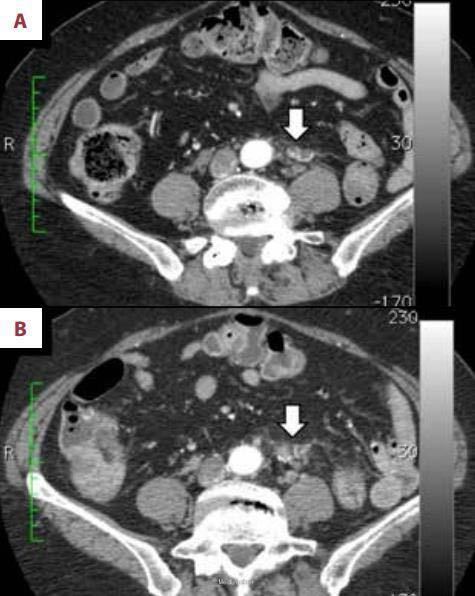

患者男性,69岁,5年前因大便带血于我院就诊,无其它不适主诉,结肠镜检查发现结肠肿瘤并肠腔狭窄,结肠镜无法通过。活检病理为高分化腺癌。CT检查示无浆膜侵袭和远处转移,临床分期为II期。行结肠癌根治术,周围淋巴结清扫。术后病理:癌灶已经侵蚀浆膜层,周围淋巴结未见转移征象,切缘阴性。术后患者每3个月来医院进行血生化复查,每6个月行腹部CT检查。 术后一年半后CT检查结果显示腹主动脉分叉处左侧见一边界模糊,非肿瘤性病灶,血供丰富(见下图1A)。考虑为术后结缔组织的炎症反应。随后几次复查发现该病灶的形态逐渐改变。术后三年CT检查结果显示病灶体积增大,但放射科医生依旧认为是良性病变(见下图1B)。最近来复查,上述病灶在CT上呈实性肿瘤样改变(见下图2A),怀疑为结肠癌术后局限性复发。但癌胚抗原和CA199都在正常范围内。为了明确诊断,患者去外院行FDG-PET/CT检查。检查结果如下图(2B),上述病灶呈明显高FDG摄取,除上述病灶外未发现其他存在病灶。